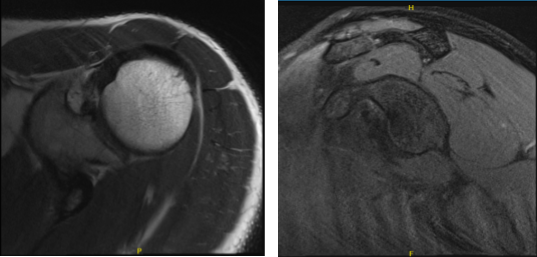

Left shoulder X Ray were presented and discussed and showed normal left shoulder radiographs. Recommended patient to undergo MRI to see the reason behind the pain. Found that there is very minimal AC joint osteoarthritis. No subacromial enthesophyte is visualized. Also noticed, mild rotator cuff tendinosis.

MRI-3T Left Shoulder Non-contrast